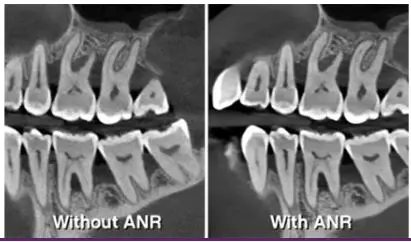

• Imágenes sin artefactos

La exclusiva tecnología CS MAR1

con comparación en tiempo real

reduce automáticamente los

artefactos metálicos para ayudar

a confirmar el diagnóstico y

minimiza el riesgo de

interpretación errónea.

• IMÁGENES 3D DE ALTA RESOLUCIÓN SIN RUIDO

A 75 micras, el sistema de CS 8200 3D ofrece imágenes de ultra alta resolución idóneas para aplicaciones de endodoncia, así mismo, el algoritmo ANR reduce el ruido de la imagen sin perder detalles clínicos.